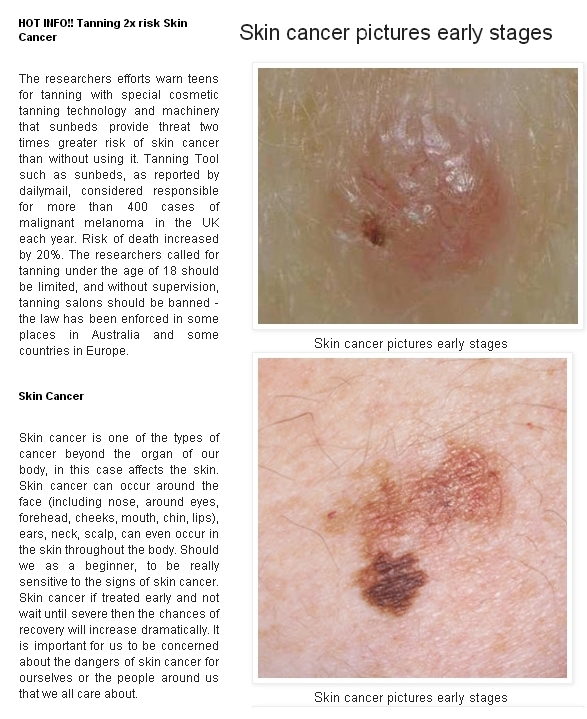

List showcases captivating images of penile cancer photos download gathered and meticulously curated by the website galleryz.online. Furthermore, you can find more related images in the details below.

penile cancer photos download

Posts: penile cancer photos download